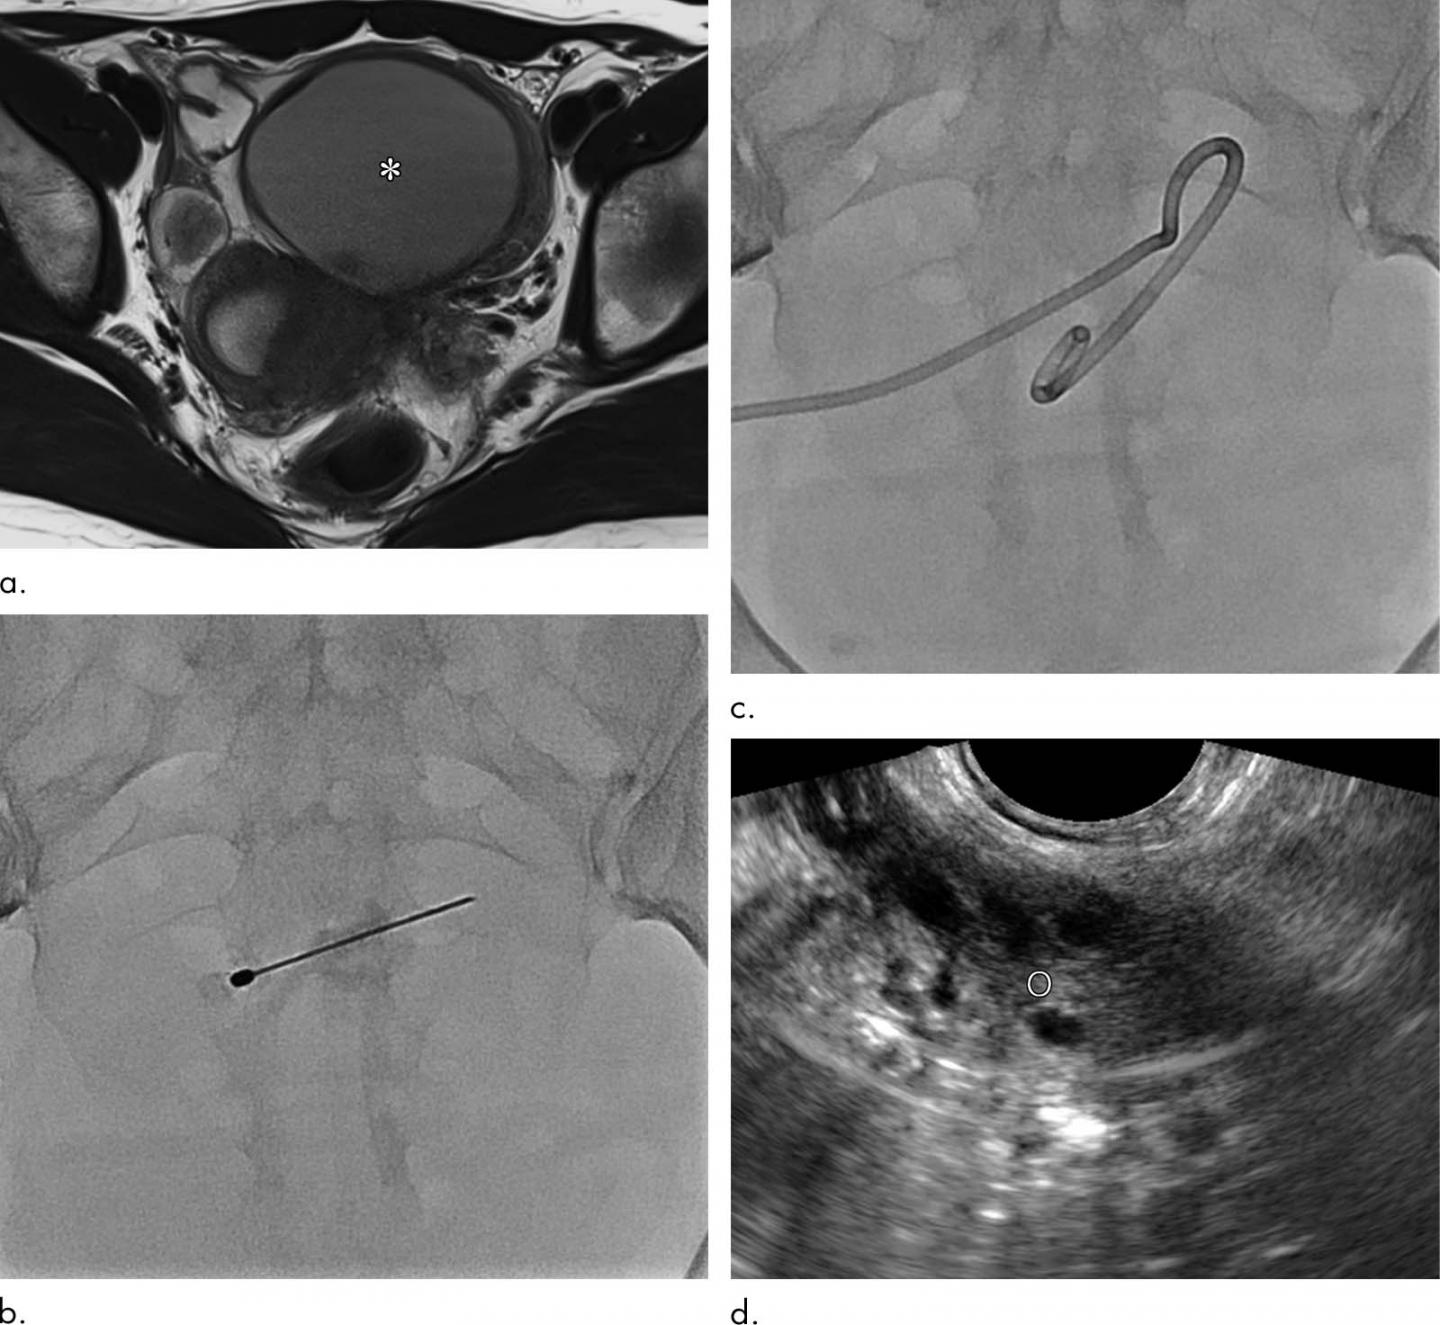

Surgery is a common treatment for endometriomas, but it carries risks, including the removal of healthy ovarian tissue, which can affect fertility. Needle-based sclerotherapy is a less-invasive option that involves inserting a needle into the cyst under ultrasound guidance and then withdrawing the cystic fluid through a needle. The cyst is then washed with a solution of ethanol. However, the needle-directed approach has limitations, said study co-author Man-Deuk Kim, M.D., Ph.D., professor at Severance Hospital, Yonsei University College of Medicine in Seoul, South Korea.

Dr. Kim and colleagues studied a sclerotherapy technique that replaces the needle with a catheter, a flexible tube used for removing fluid from cavities in the body. Along with draining cystic fluid more easily, a catheter allows for positional changes during the procedure, which helps maximize the ethanol's effectiveness by enabling it to contact the cyst wall evenly. The catheter also reduces the risk of spillage into the peritoneal cavity of the abdomen.

The researchers evaluated catheter-directed sclerotherapy with 95 percent ethanol in 14 women between the ages of 20 and 44 with ovarian endometriomas.

After about one year, the cysts had decreased on average from 5.8 centimeters (cm) in diameter to 1.1 cm. Pain was relieved in all patients, and blood tests indicated well-preserved ovarian function. There were no procedure-related complications.

There were no endometrioma recurrences, even in patients with internal septation, or division, within their cysts. The multiple compartments of septated cysts can be difficult to puncture with a needle, which may lead to incomplete sclerotherapy. In catheter-directed sclerotherapy, once the endometrioma is punctured, clinicians can manipulate the guidewire and catheter to break down internal septations, allowing for more effective treatment.